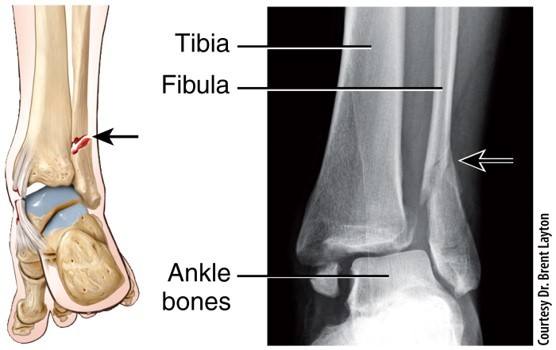

Pott Bone Fracture